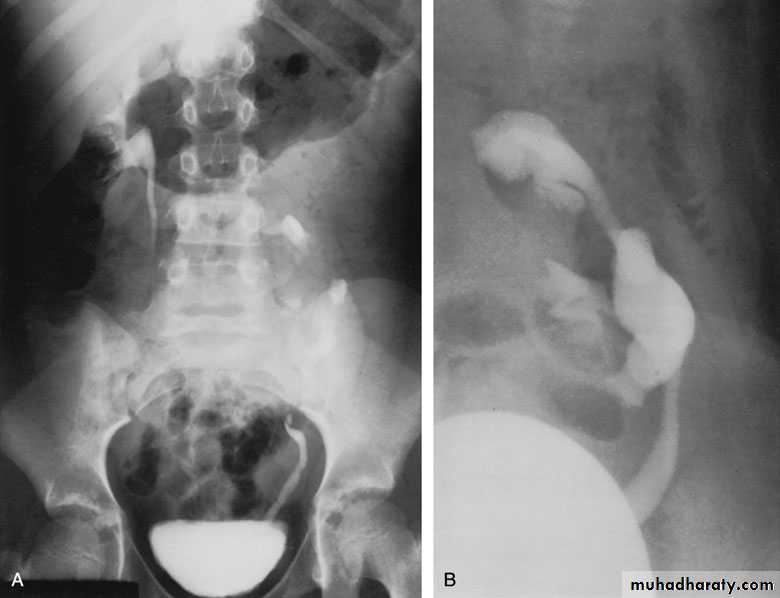

Ureteroceles

Is due to congenital atresia of the ureteric orifice which causes a cystic dilatation of the intramural portion of the ureter

Women > men

Sometimes involves with ectopic ureter

More prone to stone disease & UTIs

Clinical Features : Asymptomatic

Repeated UTIs, Hematuria

Diagnosis:

IVU, cystoscopy, cystogram

The ‘adder head’ on excretory urography is typical.

Treatment:

Asymptomatic : no treatment

Cystoscopy with diathermy cauterization of the hole

Nephrectomy in non functioning kidney

In complicated cases, ureteral reimplantation and vesical reconstruction

Cobra (Adder) head appearance of ureterocele

Ureterocele involving single system Ureterocele involving duplicated ureter